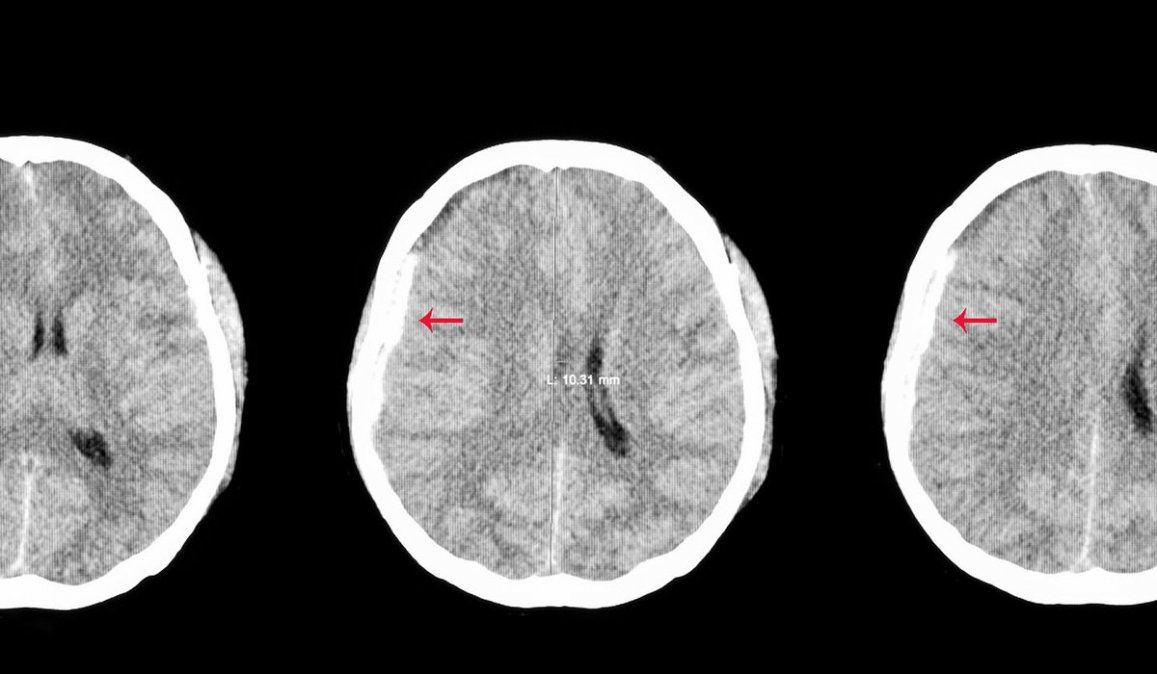

Sobre el hematoma subdural que tiene explicó: "Hace un mes hicimos una tomografía normal, decidimos repetirla y tiene un hematoma subdural, de superficie, que crece paulatinamente. Es una cirugía de rutina, la ha tenido la vicepresidenta (Cristina Kirchner)".

Es una acumulación de sangre entre la cubierta del cerebro (duramadre) y la superficie del cerebro. Puede producirse después de un traumatismo craneal, por un golpe. El sangrado llena la zona cerebral rápidamente y comprime el tejido cerebral.